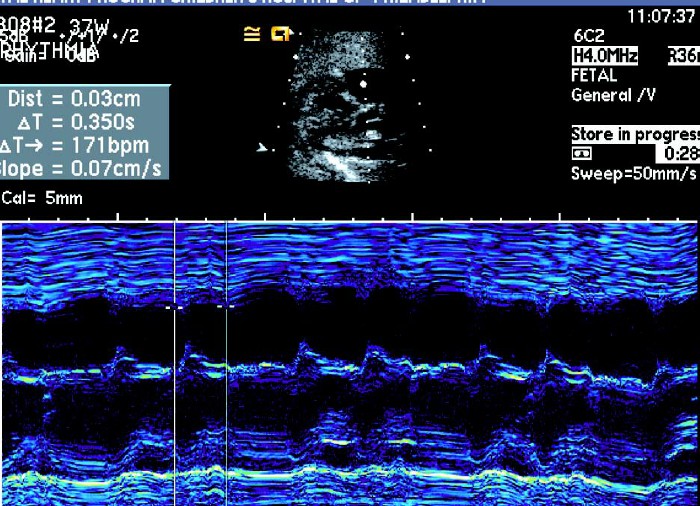

1.快速心律失常:胎儿心率>180 次/min,持续时间>5 min,即可诊断心动过速。

①室上性心动过速:室上性心动过速通常为1:1 房室传导,心率在240 ~ 260 次/ 分。